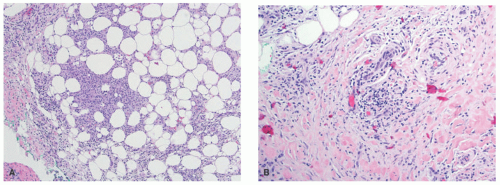

EN is the prototypical septal panniculitis, characterized histologically by a widening of, and inflammation in, the subcutaneous fat septae, with associated septal fibrosis. One often appreciates “spill-over” inflammation into the surrounding fat lobules as well, but low-power microscopic examination usually clearly demonstrates septal involvement as the primary process. The inflammatory cell infiltrate is composed of lymphocytes and histiocytes (Figure 5-2). In acute disease, a varying number of neutrophils and eosinophils are often present, and vasculitis may rarely be noted. Small granulomas formed by the aggregates of histiocytes surrounding a central cleft (so-called Miescher’s radial granulomas) are often present; they are common in, but not pathognomonic for, EN, and can be seen in other forms of panniculitis, as well as in neutrophilic dermatoses and necrobiosis lipoidica (NL) diabeticorum.4,5

![]() FIGURE 5-2. Erythema nodosum histopathology: widening and chronic inflammation of the subcutaneous fat septae. |